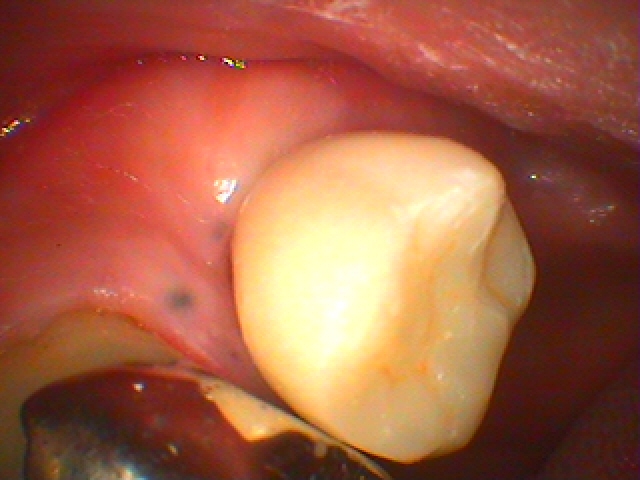

インプラントの上部構造もセラミックにて作成していきます。 1本30万円。| |広島市安佐南区の歯科医院 インプラントの上部構造もセラミックにて作成していきます。 1本30万円。 トップ お知らせ・ブログ インプラントの上部構造もセラミックにて作成していきます。 1本30万円。 インプラントの上部構造もセラミックにて作成していきます。 1本30万円。 Web診療予約 初めての方へ 選ばれ続ける理由 院内設備について 歯が痛いしみる一般歯科 歯がぐらぐらする歯周病 健康な歯を保ちたい予防歯科 子供の虫歯予防をしたい小児歯科 銀歯をセラミックに審美歯科 白い歯を目指しませんか?ホワイトニング 矯正専門医がいるので安心矯正歯科 抜けた歯を補いたいインプラント・入れ歯 医院案内 スタッフ紹介 メリィハウス歯科クリニックオフィシャルホームページ ラベンダー歯科クリニックオフィシャルホームページ お知らせ・ブログ ホーム 診療科目 一般歯科 歯周病治療 予防治療 小児歯科 審美治療 ホワイトニング 矯正歯科 入れ歯・インプラント マウスピース矯正 初めての方へ 院長・スタッフ 設備紹介 医院案内・アクセス メニューを閉じる